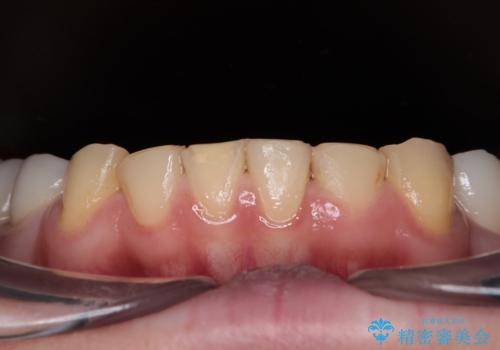

- 一時期の拒食症に伴い歯が酸で溶けてボロボロになってしまったとのことで来院された患者様です。

酸によりエナメル質の大半が溶けており、下顎前歯以外は酷いむし歯のような状態でした。

矯正治療終了後に、残った歯をオールセラミッククラウンにて補綴治療を行うこととしました。

途中来院が困難な時期があったり、歯周外科処置を行って治癒を待ったりと、治療期間は長くなりましたが、初診時とは比べものにならないくらいきれいに仕上げることができました。